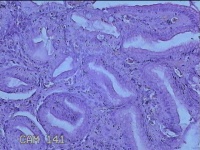

胃窦粘膜

性别

女

年龄

30岁

临床诊断

慢性胃炎;胃食管反流

一般病史

上腹部疼痛1周余。

标本名称

大体所见

灰白粉红色组织小米大一团。